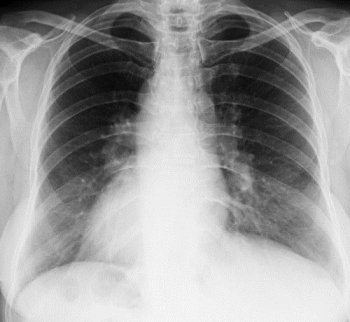

Из-за высокой смертности, связанной с заболеванием, главной задачей врача-пульмонолога является правильная диагностика двусторонней пневмонии. Специалисты хорошо осведомлены о природе этого заболевания и его последствиях. Поэтому, помимо устного опроса пациента, необходимо использовать и другие методы для установления диагноза.

Методы диагностирования:

- Общий анализ крови

- Рентгеновское исследование

- Микроскопия и посев мокроты

- Ультразвуковое исследование сердца

- Ультразвуковая диагностика

- Бронхоскопия

- Компьютерная томография грудной клетки

- Бактериологическое исследование мокроты

Вне зависимости от причины, пневмония — серьезная болезнь, которую нельзя пытаться лечить самостоятельно. При первых подозрениях необходимо как можно быстрее обратиться к врачу. Определить болезнь можно с помощью рентгенографии или компьютерной томографии легких.